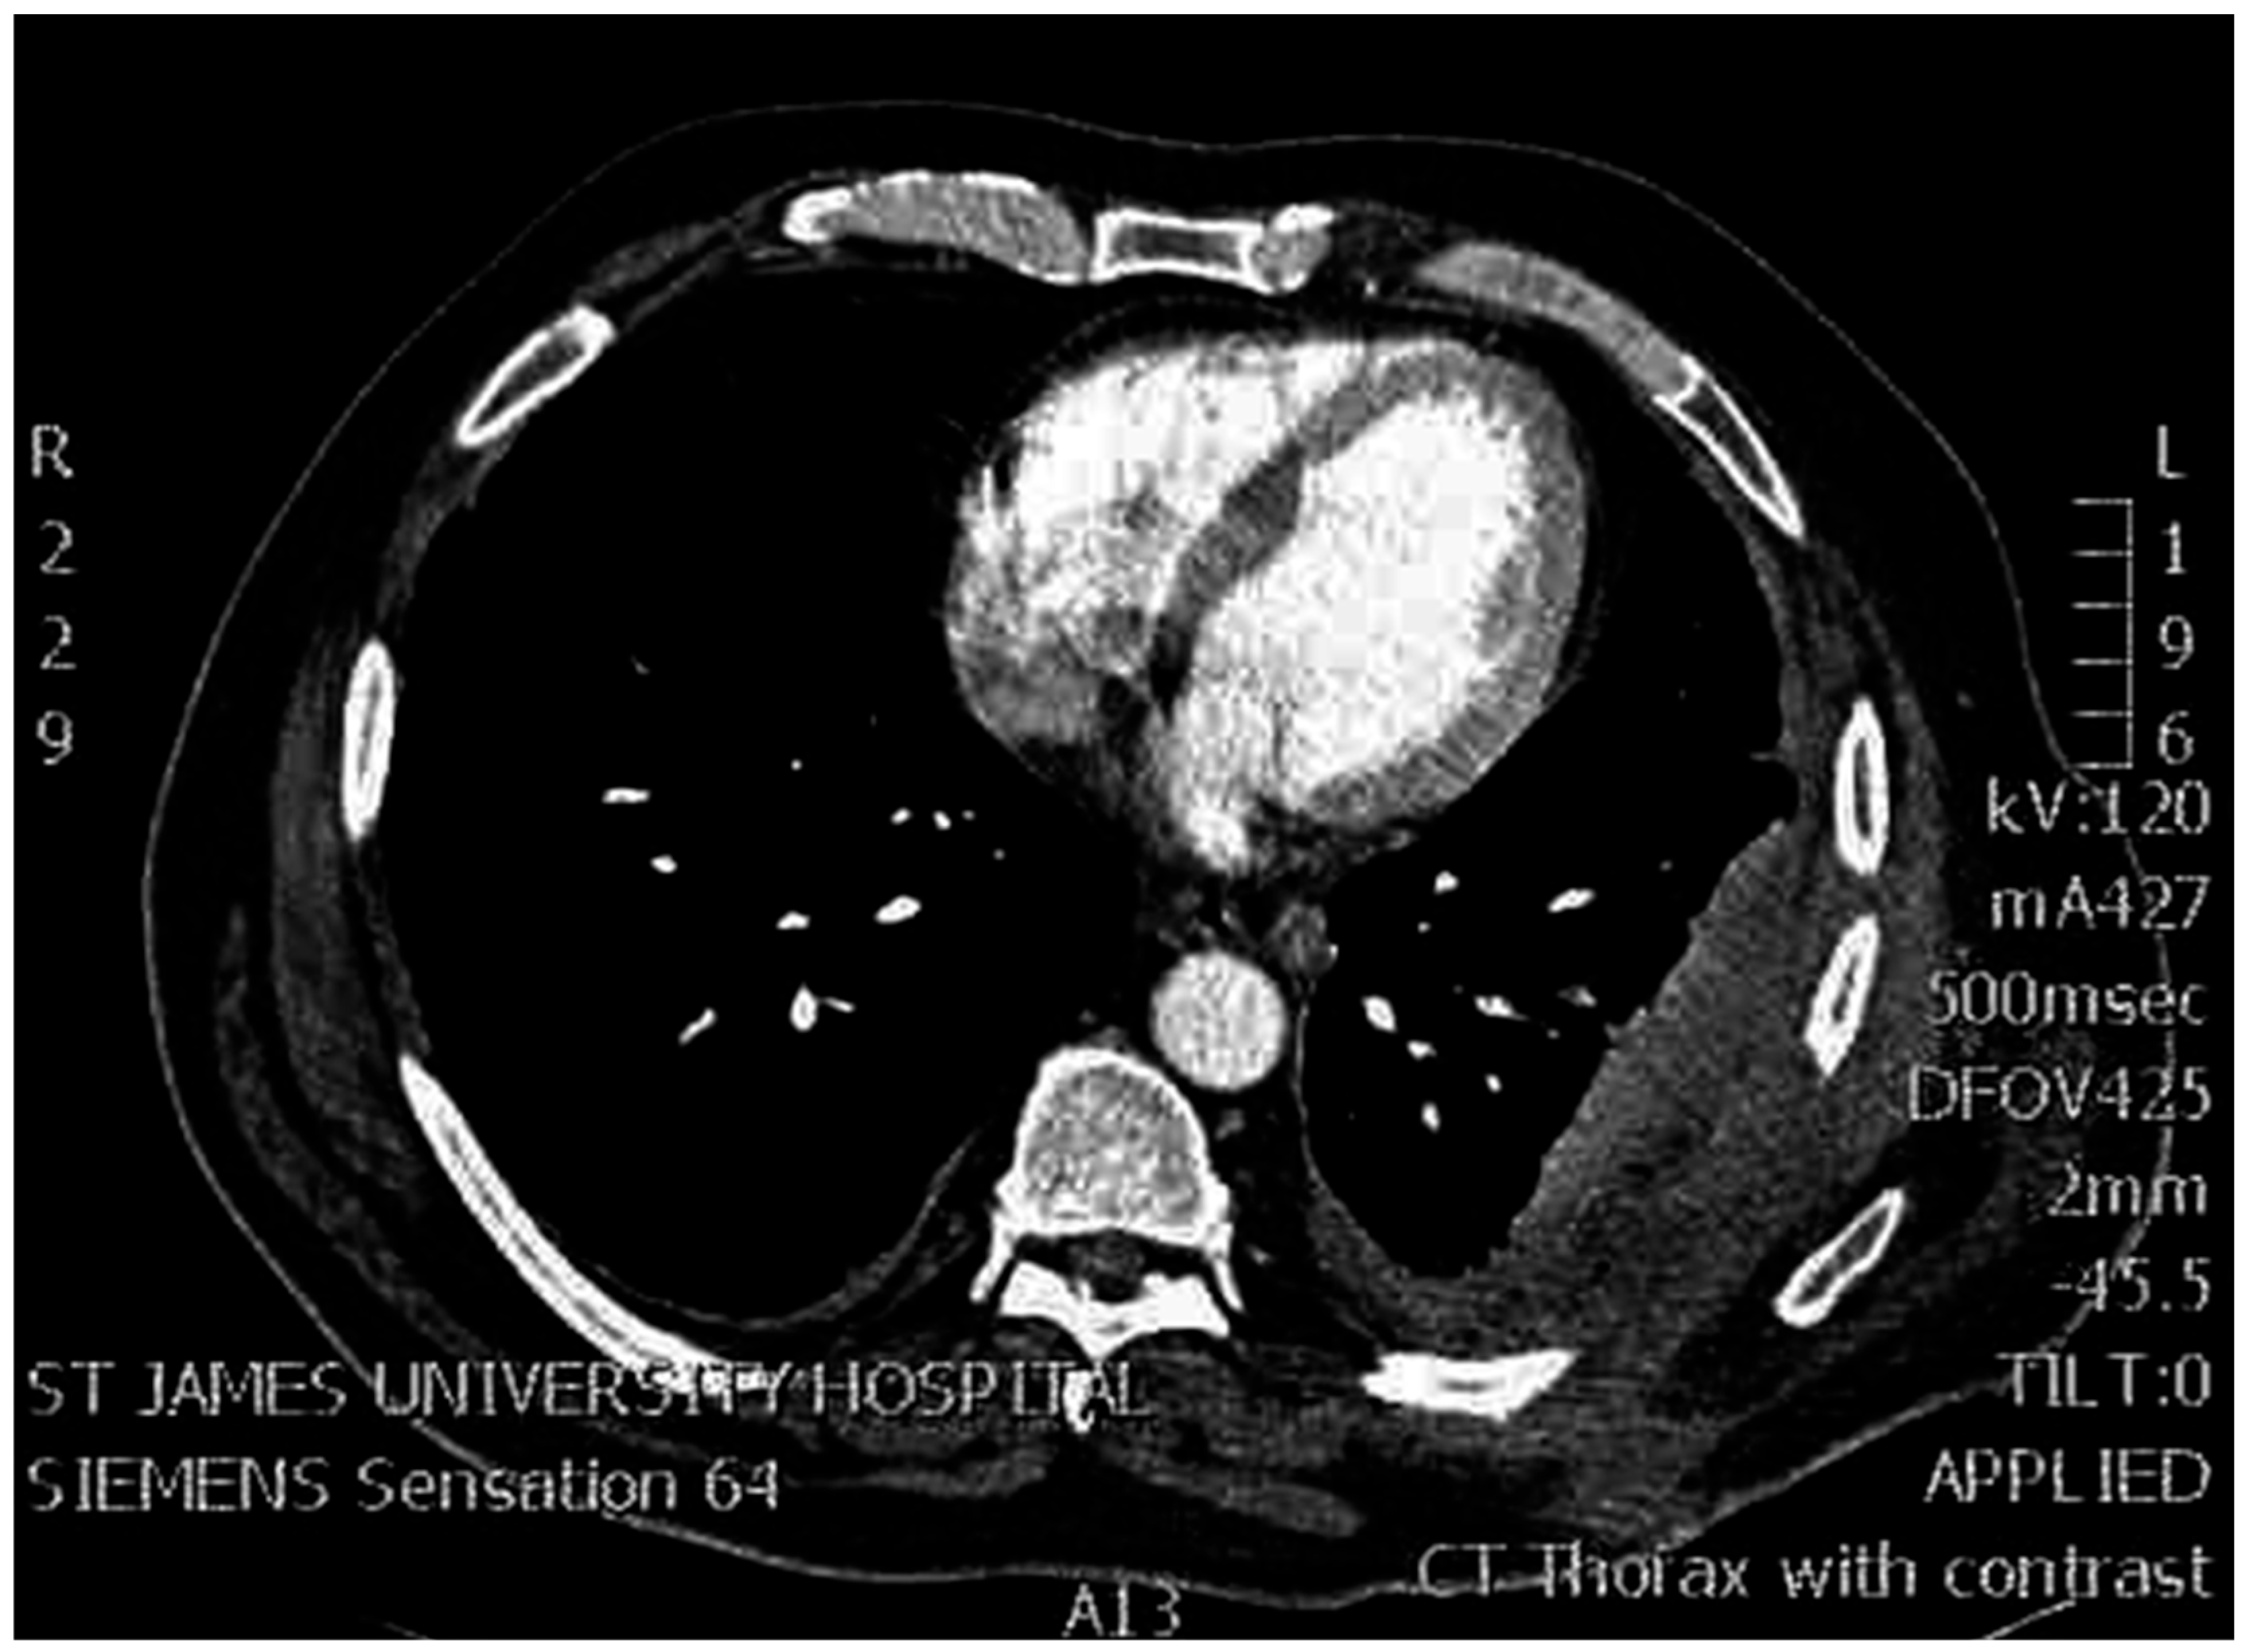

Regarding surgical planning and decision making, a CT scan is mandatory as is required for all thoracoplastic procedures. The thoracotomy incision should correlate to the location of the infected pleural space. Thus, we should be ready to tailor our approach into atypical thoracotomies. The large muscles of the thorax—latissimus dorsi and serratus anterior—should ideally be preserved for flap use if required as in two of our patients. Gentle ventilation is used to define the volume and position of this space, and to identify the exact position of the thoracoplastic ‘patch’. During the procedure, periosteal rib stripping should be generous enough to comfortably fill the cavity without tension. The integrity of the intercostal neurovascular bundles should be respected to prevent tissue ischemia. All soft tissues of the chest wall should be preserved as a single sheet, and the thoracotomy incision sealed without any extra-pleural communication. Moreover, this space must be adequately drained to avoid hematoma formation. Moderate parenchymal leaks should no longer be of concern as long as the collapsed chest wall elements cover the lung parenchyma. After the operation, the extraperiosteal space fills with exudate which exerts pressure on the collapsed chest wall elements facilitating the obliteration of the cavity of empyema. In the following months, the exudate is absorbed as the lung re-expands [17,18]. Figure 5. shows a CT scan of a patient after Sawamura thoracoplasty with obliterated pleural space. At the end of the procedure, at least one intrapleural and one extrapleural chest drain are required. We recommend applying suction on both drains, until drainage is diminished and the lung expands on chest films. Patients should undergo early postoperative mobilization, aggressive pulmonary expectoration, shoulder mobilization, adequate pain management by combination of analgesics and nutritional support. Antibiotic treatment is culture-guided by the intraoperative obtained samples, especially if multi-resistant strains have been isolated.

Figure 5. A post-operative CT scan from the archive of our clinic showing complete obliteration of the pleural space and opposition of soft chest wall elements with the partially collapsed left lower lobe.